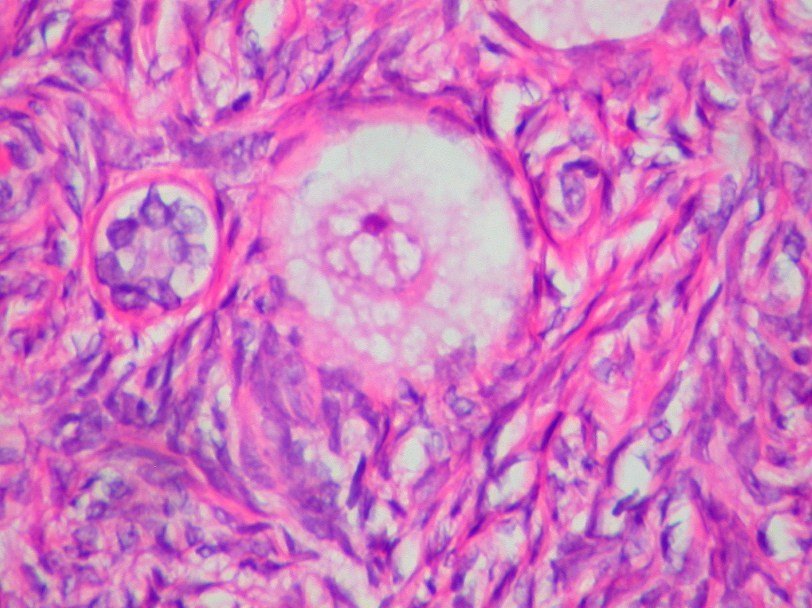

Препарат ткани яичника женщины, проходившей химиотерапию по схеме ABVD, (слева вверху), содержит больше фолликулов, в каждом из которых находится ооцит, чем ткани других женщин.

Чтобы ответить на этот вопрос, они брали биопсию яичников у женщин, проходивших курс такого лечения. В исследовании участвовали восемь пациенток, получавших препараты по схеме ABVD, три женщины, чей курс лечения был построен по другой схеме (OEPA-COPDAC), а также десять здоровых женщин. При изучении препаратов оказалось, что количество ооцитов у них значительно (от двух до четырех раз) больше, чем у здоровых женщин того же возраста. Эвелин Тефлер рассказывает изданию The Guardian: «Это было что-то замечательное и совершенно неожиданное для нас. В тканях, по-видимому, образуются новые яйцеклетки. Считалось догмой, что в человеческих яичниках есть фиксированное количество яйцеклеток и никакие новые не могут формироваться на протяжении всей жизни».